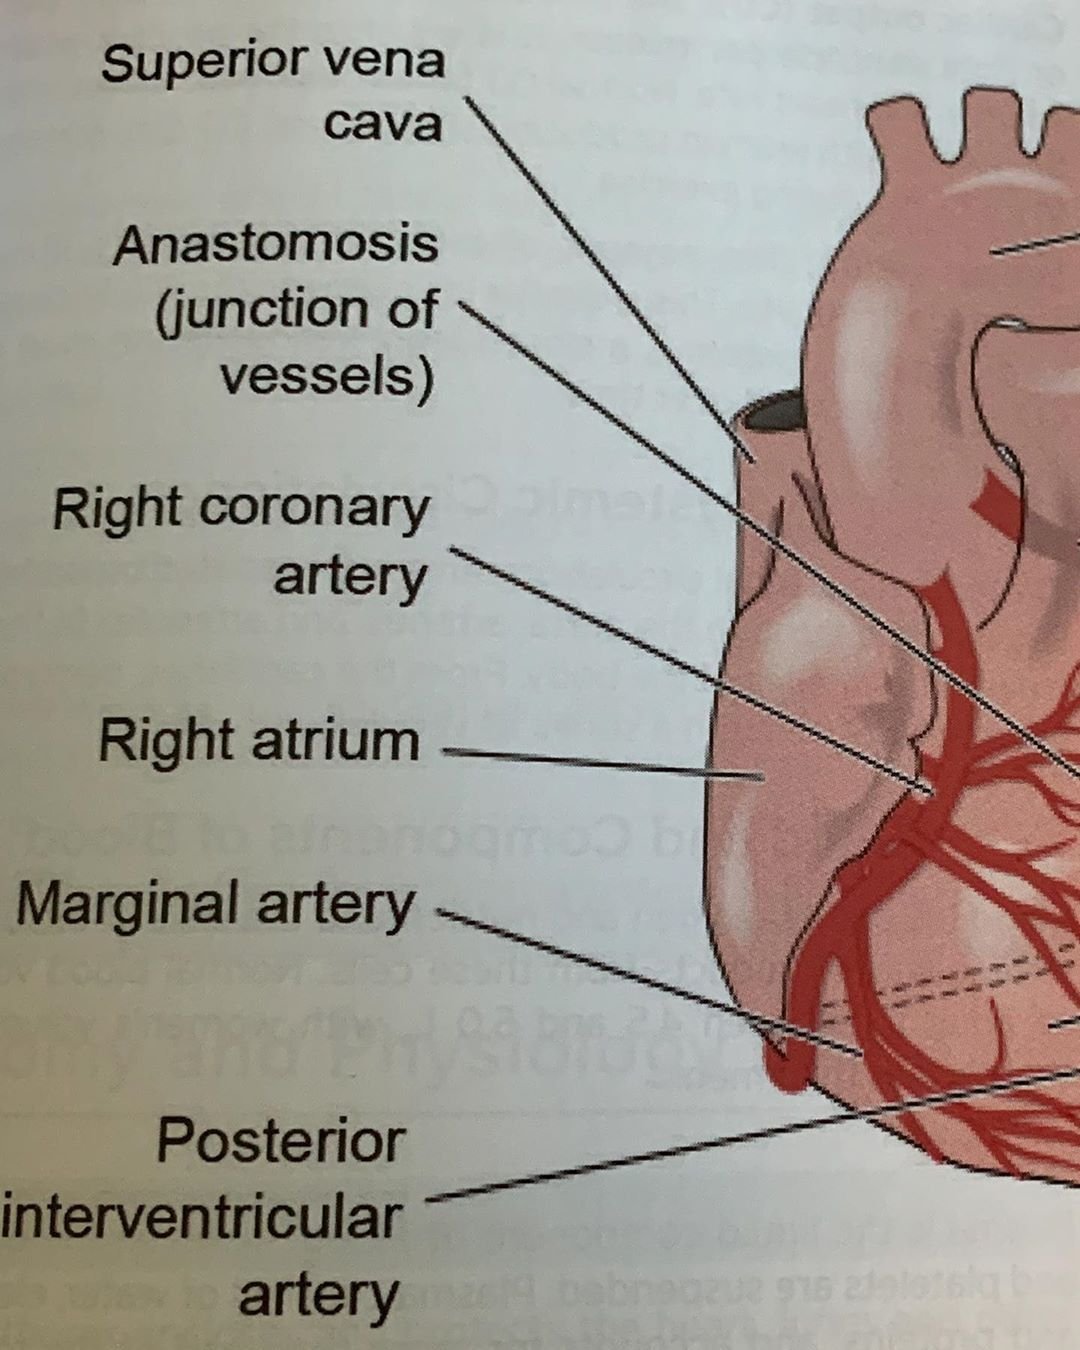

Анатомия коронарных артерий: КТ-изображения